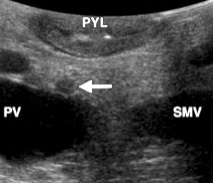

Describe this image

Diagnosis?

Transverse view of the pancreas

Pancreas appears to be swollen/enlarged with increased echogenicity and has peripancreatic fluid

Dx: acute pancreatitis